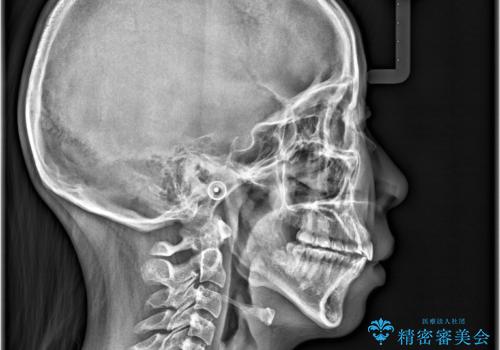

- 「歯の捻じれとがたつき」を主訴に来院された患者様です。

軽度な捻転と叢生だったため、インビザラインのモデレートで治療を行いわずか半年で治療を終える事が出来ました!